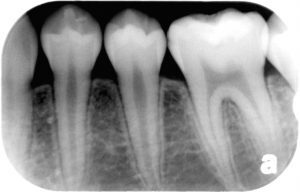

しかし、虫歯ではないので初期の場合、レントゲンでは悪くなった状態がわからないこともあります。歯医者でも知覚過敏や歯ぎしりなどとの違いに診断を下すのが難しい場合があります。

上で上げている写真のお子さんも、実は中心結節が折れていましたが、レントゲン写真より神経は中になく症状もなかったので一安心でした。

歯を見てみると中心結節が折れており、X線写真をとってみると神経が死んでしまい、左下の小臼歯から膿がたまっていた状態でした。

この場合は歯の根が感染していたため通常の治療を行いましたが、年齢も若く根が出来上がっていませんでした。

ですので、半年ほど特殊なお薬をもちいて根を封鎖してから、お薬を詰めてしっかり噛んでいただいております。